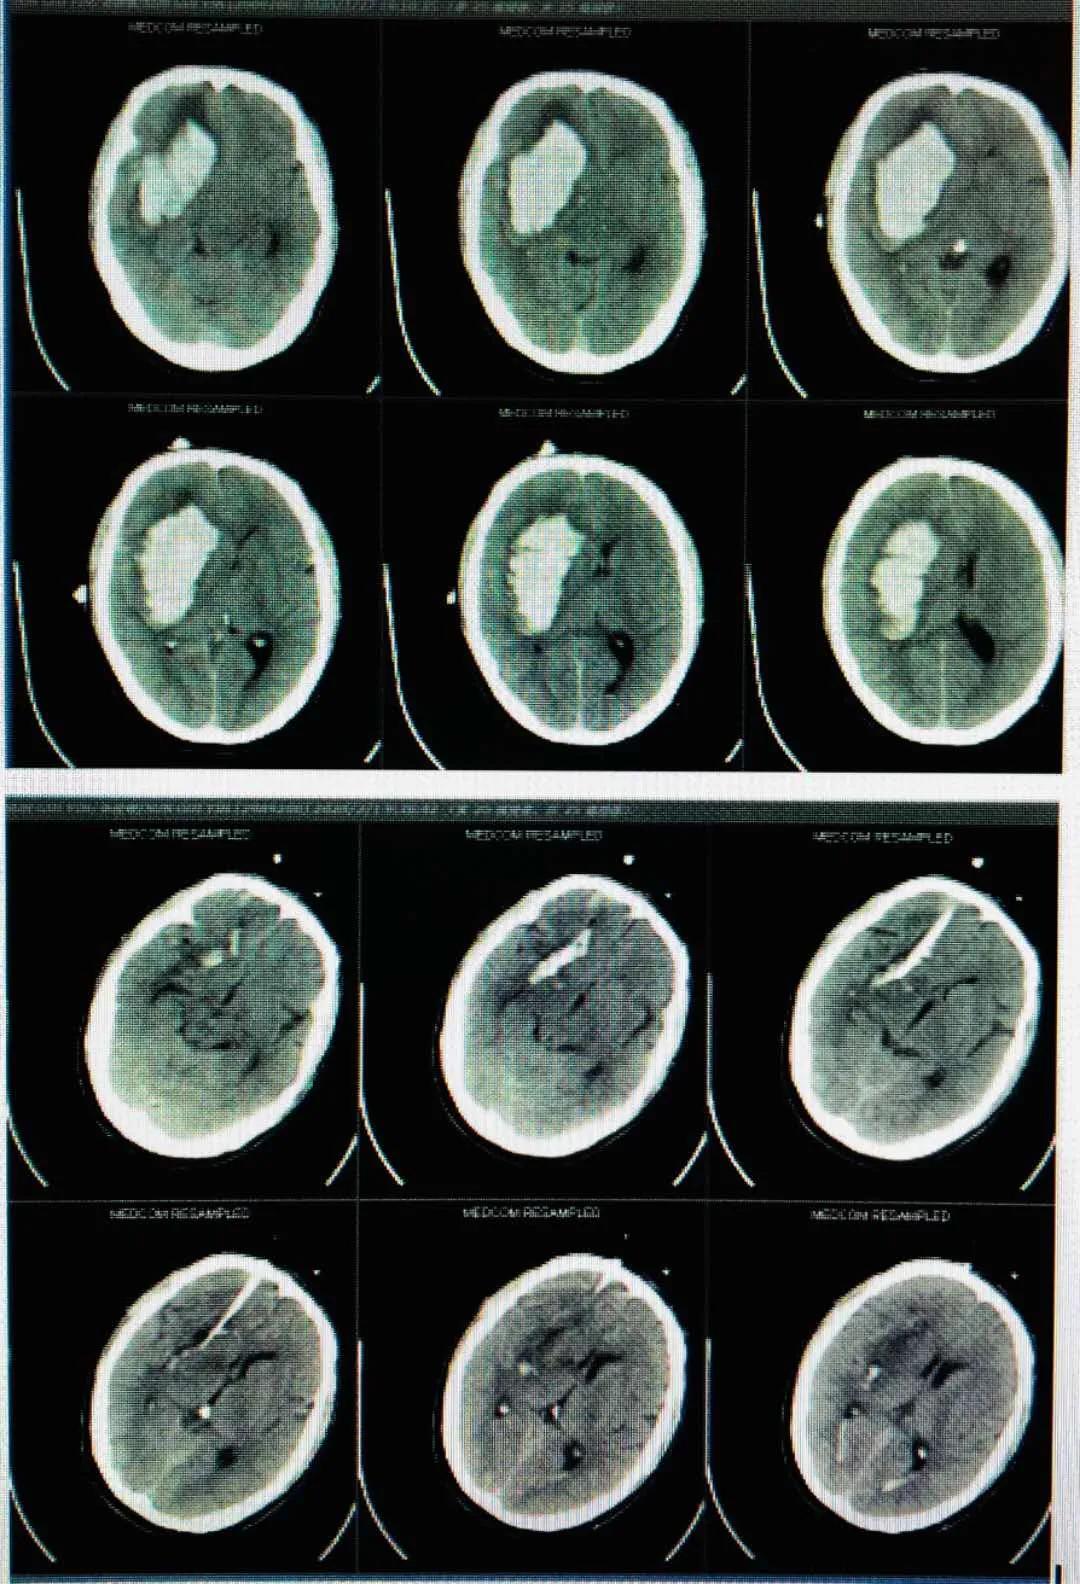

患者高某,男性,73岁,于入院2个半月前因外伤致伤头部,当即人事不省,无口吐白沫、双眼上吊、四肢抽搐,无大、小便*禁失**等不适,经福建医科大学附属第一医院治疗后好转。1个月前就诊我院康复科,行康复治疗。半个月前患者开始出现精神状态欠佳,呈痴呆状,意识障碍,大、小便*禁失**。诊断为创伤性脑积水、左侧额部硬膜下积液、右侧颞叶软化灶、两肺下叶炎症。5月18日在局部麻醉下行“脑室腹腔分流术”。

术后,给予预防感染和抗癫痫等对症支持处理,患者病情慢慢恢复。

脑出血脑室引流术

此外,永春县医院还成功开展了“脑出血脑室引流术”。